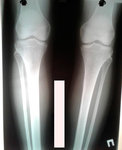

Дата операции - 04.04.2019г.

Дата снятия аппаратов - 02.07.2019г.

Срок сращения - 89 дней.